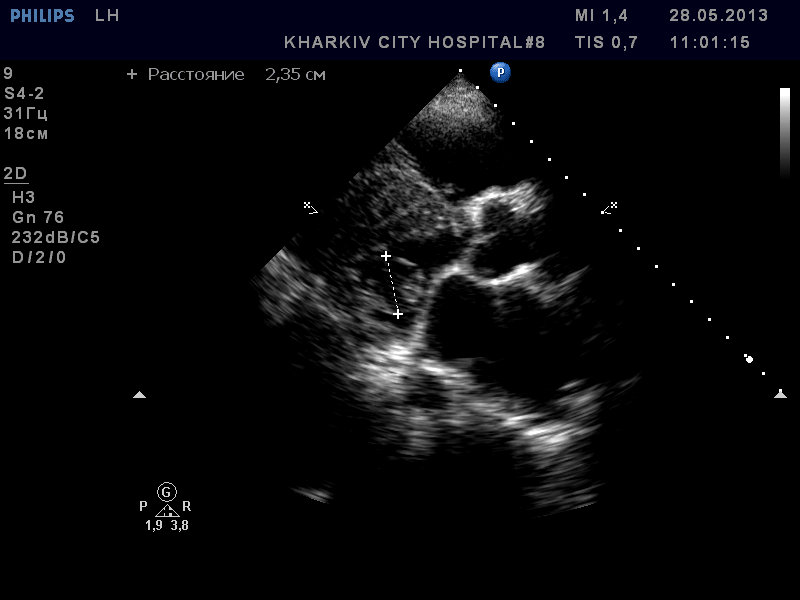

Пациентка 83 лет. Жалобы на сильную одышку в теч. последнего месяца.

В полости левого желудочка в базальном сегменте имеется образование с неровным контуром до 2.4см- вероятно миксома левого желудочка.

кальциноз створок АК, дилатация левого предсердия, правых полостей, выраженная недостаточность ТК и клапана ЛА, гипертрофия левого желудочка. Дополнительные косые хорды левого желудочка. Высокая ЛГ (АТ/ЕТ- 0.20 Рсред. ЛА-69мм рт.ст.).